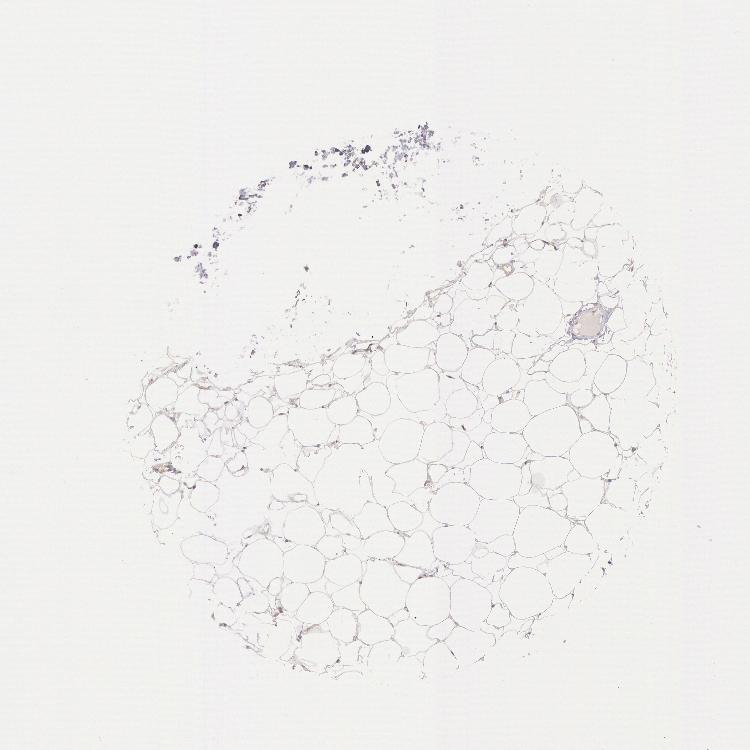

TISSUE PRIMARY DATA ADIPOSE TISSUE Show tissue menu

ADIPOSE TISSUE - Expression summary

Protein expression

Adipose tissuei

On the top, protein expression in current human tissue, based on all annotated cell types, is reported with the units not detected (n), low (l), medium (m) and high (h). Underneath, protein expression in each annotated cell type are reported using the same units.

Protein expression data is based on knowledge-based annotation. For genes where more than one antibody has been used, a collective score is set.

If knowledge-based annotation could not be performed for a gene, no data is displayed here. View antibody staining data further down this page.

Adipocytes: Low

ADIPOSE TISSUE - Antibody stainingi

Antibody staining in the annotated cell types in the current human tissue is reported as not detected, low, medium, or high, based on conventional immunohistochemistry profiling in selected tissues. This score is based on the combination of the staining intensity and fraction of stained cells.

Each image is clickable and will lead to virtual microscopy that enables deeper exploration of all samples and also displays staining intensity scores, fraction scores and subcellular localization as well as patient and tissue information for each sample.

Antibody HPA001275Antibody CAB017442

Adipocytes LowLow